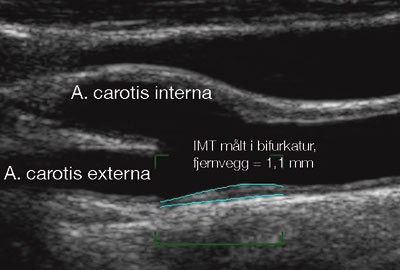

Ultralyd kan med høy grad av presisjon diagnostisere stenoser i de precerebrale halskar samt i de store intrakraniale arteriene på hjernens basis. Det er godt samsvar mellom funn ved ultralyd og angiografi, og ultralydundersøkelse utelukker > 70 % stenosegrad med en sensitivitet på 98 % vurdert mot angiografi (20). Ultralyd er også velegnet til å vurdere det aterosklerotiske plakks morfologi. Fordi a. carotis ligger nær ultralydhodet, kan man bruke høyere ultralydbølgefrekvens enn ved undersøkelser av hjertet og abdomen, hvilket gir betydelig bedre bildeoppløselighet. Intima-media-tykkelsen (IMT), som er avstanden fra karlumen til adventitia (fig 1 og 3) og som innbefatter intima og media, måles best i fjernveggen distalt i a. carotis communis men, tykkelsen kan også bedømmes i carotisbifurkaturen og proksimalt i a. carotis interna (21).

Måling av IMT er mye benyttet i epidemiologisk ateroskleroseforskning, som i den kjente norske Tromsøundersøkelsen. Høy IMT-verdi, samt stigende IMT-verdi over tid, er assosiert med de etablerte risikofaktorene for aterosklerose. Forhøyet IMT-verdi er også assosiert med utvikling av plakk, og med utbredelse av aterosklerose til andre karområder (21) – (23). IMT-målinger er blitt bruk som pseudoendepunkt ved intervensjonsstudier. IMT kan reduseres ved senking av LDL-kolesterol, ved bruk av statiner samt under blodtrykksbehandling (24, 25). Metoden kan dog ikke benyttes til å følge behandlingseffekten hos den enkelte pasient, til dette er forandringene over tid for små og variansen mellom enkeltmålinger for stor. Forhøyet IMT-verdi er assosiert med senere koronare og cerebrovaskulære hendelser, også etter korreksjon for tradisjonelle risikofaktorer (26). En vesentlig andel av variasjonen i IMT fra person til person kan forklares genetisk (27). Nyere studier har vist at proinflammatoriske genvariater sammen med røyking og diabetes mellitus også har en synergistisk effekt på økning i tykkelse (28). Vurdering av IMT i carotisarteriene synes å gi like god estimering av risikoen for senere aterosklerotiske komplikasjoner som bruk av alle de kjente risikofaktorer til sammen (29). Det er også kommet studier som postulerer at faren for fremtidige hendelser predikeres aller best når ultralydundersøkelse av de precerebrale halskar kombineres med en risikoskåring etter Framinghamskalaen (30, 31).